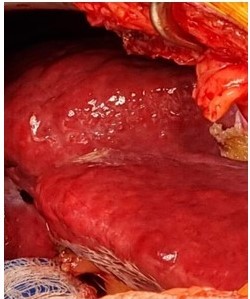

En cirugía se realizó laparotomía exploradora bajo incisión de Kocher se evidenció 1. Hígado micro-nodular, de bordes irregulares, aumentado de consistencia (Figura 5) 2. Lesión de ocupación de espacio (LOE) de 7 cm x 7 cm que abarca segmento V y VI (Figura 6) 3. No se evidenciaron otras lesiones palpables o visibles en hígado o peritoneo. 4. Ecografía intra-operatoria sin otras lesiones satélites. Se realiza movilización de lóbulo hepático derecho con sección de ligamentos coronarios y triangular derecho con Harmonic®, se realiza demarcación con electro bisturí de bordes a 2 cm de la lesión, posteriormente se realiza incisión con Cusa Excel® en bordes delimitados, realizando hemostasia con Argon Plasma® y Harmonic ® hasta planos profundos donde se realiza sección hepática de segmento V y VI con Echelon® cartucho 45 mm blanco, se extrae pieza que se envía para estudio extemporáneo el cual reporta márgenes negativos para malignidad. La evolución posoperatoria fue satisfactoria por lo cual fue egresado al cuarto día posoperatorio.